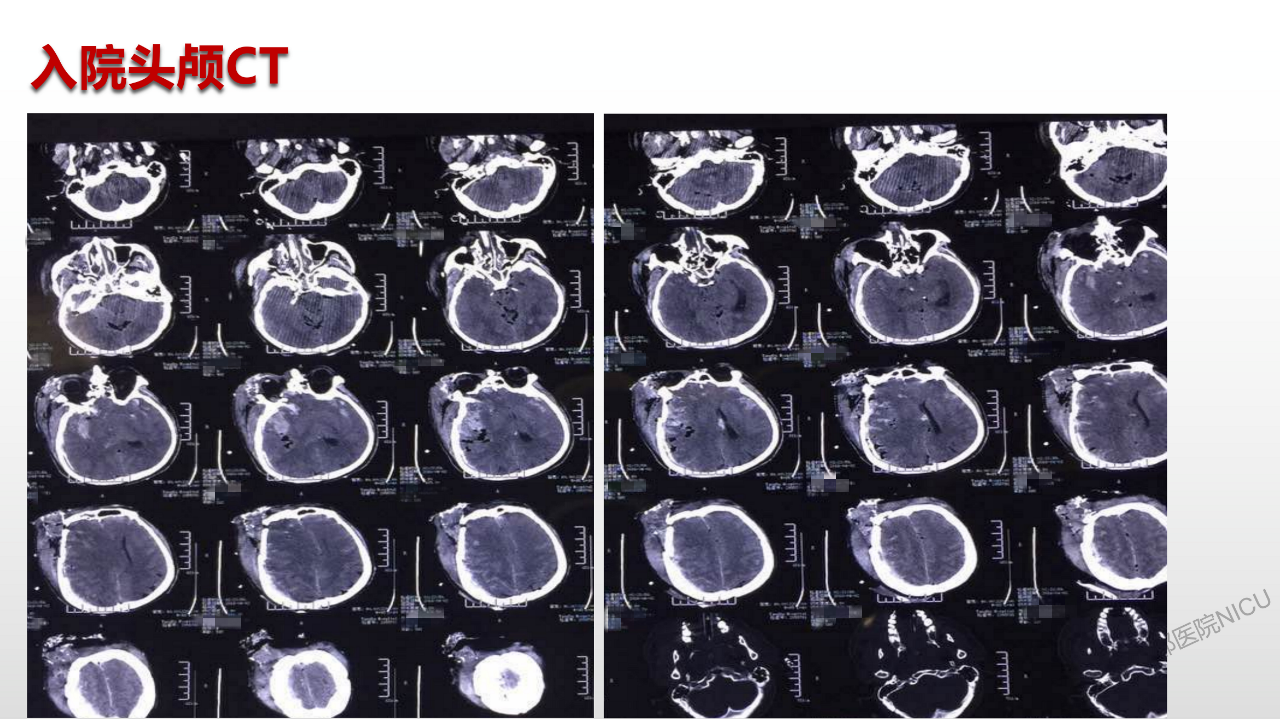

特重型颅脑外伤后难治性高颅压报告一例

课件展示